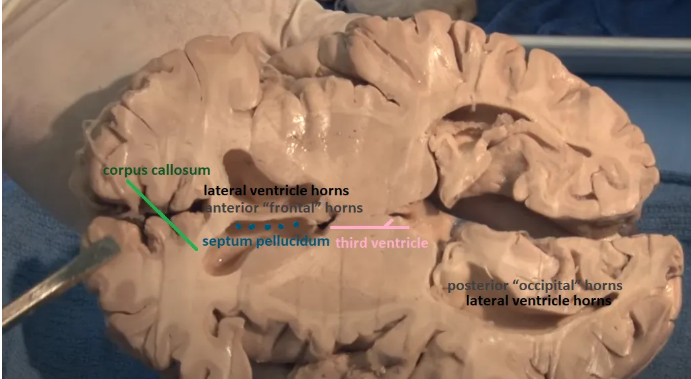

Thalamus (pink) and hypothalamus (yellow): their medial surfaces border the third ventricle (blue).

The purple hippocampus is visualized tracing the ventricular system (turquoise).